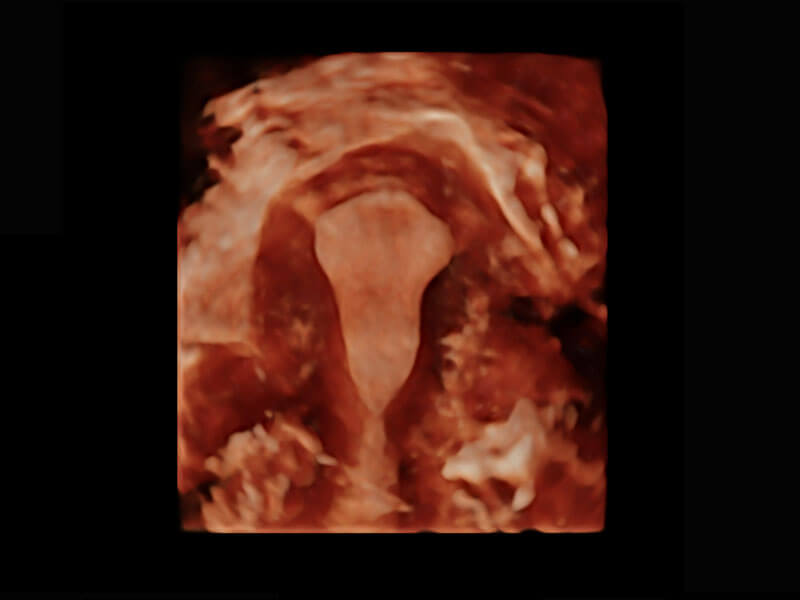

生殖健康

P60优异的图像质量搭载专科探头,在妇科基础疾病的诊断、卵泡生长的监测、输卵管通畅情况的判别等方面为您提供生殖应用方案。

• 腔内三维-宫内节育器

• 腔内三维-光影成像